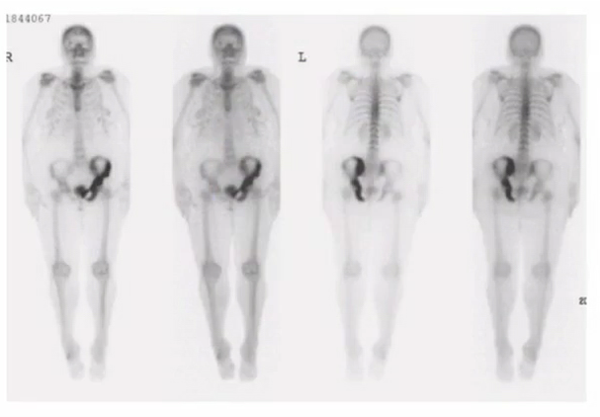

sacral insufficiency fracture